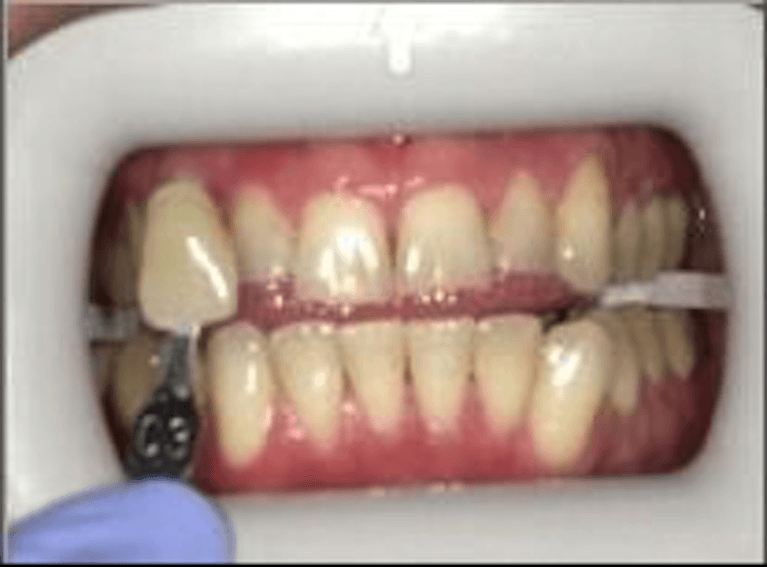

This patient wanted a brighter, more youthful smile for an upcoming event. Using Zoom! In-Office Teeth Whitening, we were able to lift years of surface stains in a single visit. As shown by the clinical shade guide, their smile moved several shades lighter, resulting in a brilliant, radiant finish that looks completely natural.